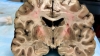

Colocado sobre una mesa de laboratorio, horas después de su muerte, el cerebro de Aaron Hernández ofrecía una apariencia saludable.